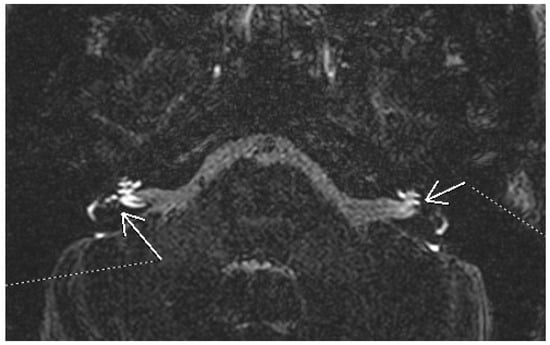

3.1.4. Acoustic Neuroma

- Belden, C.J.; Weg, N.; Minor, L.B.; Zinreich, S.J. CT Evaluation of Bone Dehiscence of the Superior Semicircular Canal as a Cause of Sound- and/or Pressure-induced Vertigo. Radiology 2003, 226, 337–343. [Google Scholar] [CrossRef]

- Diaz, M.P.; Lesser, J.C.C.; Alarcón, A.V. Superior Semicircular Canal Dehiscence Syndrome—Diagnosis and Surgical Management. Int. Arch. Otorhinolaryngol. 2017, 21, 195–198. [Google Scholar] [CrossRef]

- Minor, L.B. Superior canal dehiscence syndrome. Am. J. Otol. 2000, 1, 9–19. [Google Scholar] [CrossRef]

- Chien, W.W.; Carey, J.P.; Minor, L.B. Canal dehiscence. Curr. Opin. Neurol. 2011, 24, 25–31. [Google Scholar] [CrossRef]

- Ward, B.K.; van de Berg, R.; van Rompaey, V.; Bisdorff, A.; Hullar, T.E.; Welgampola, M.S.; Carey, J.P. Superior semicircular canal dehiscence syndrome: Diagnostic criteria consensus document of the committee for the classification of vestibular disorders of the Bárány Society. J. Vestib. Res. 2021, 31, 131–141. [Google Scholar] [CrossRef]

- Noij, K.S.; Rauch, S.D. Vestibular Evoked Myogenic Potential (VEMP) Testing for Diagnosis of Superior Semicircular Canal Dehiscence. Front. Neurol. 2020, 11, 695. [Google Scholar] [CrossRef] [PubMed]

- Browaeys, P.; Larson, T.; Wong, M.; Patel, U. Can MRI Replace CT in Evaluating Semicircular Canal Dehiscence? Am. J. Neuroradiol. 2013, 34, 1421–1427. [Google Scholar] [CrossRef]